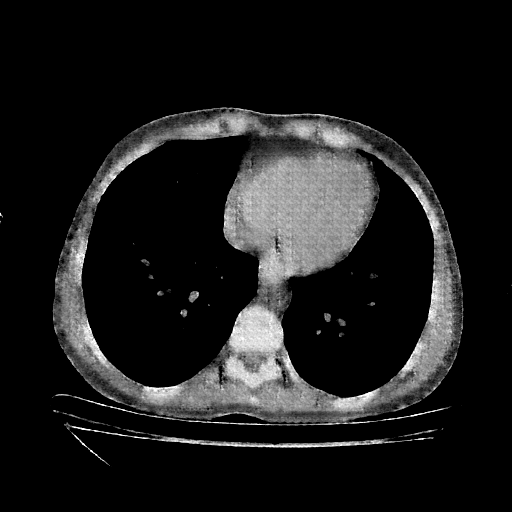

Original NATIVE CT scan (input)

No window - Raw intensity values

Lung window (WL -600, WW 1500 β†’ Low βˆ’1350, High +150)

Mediastinum window (WL 40, WW 400 β†’ Low βˆ’160, High +240)